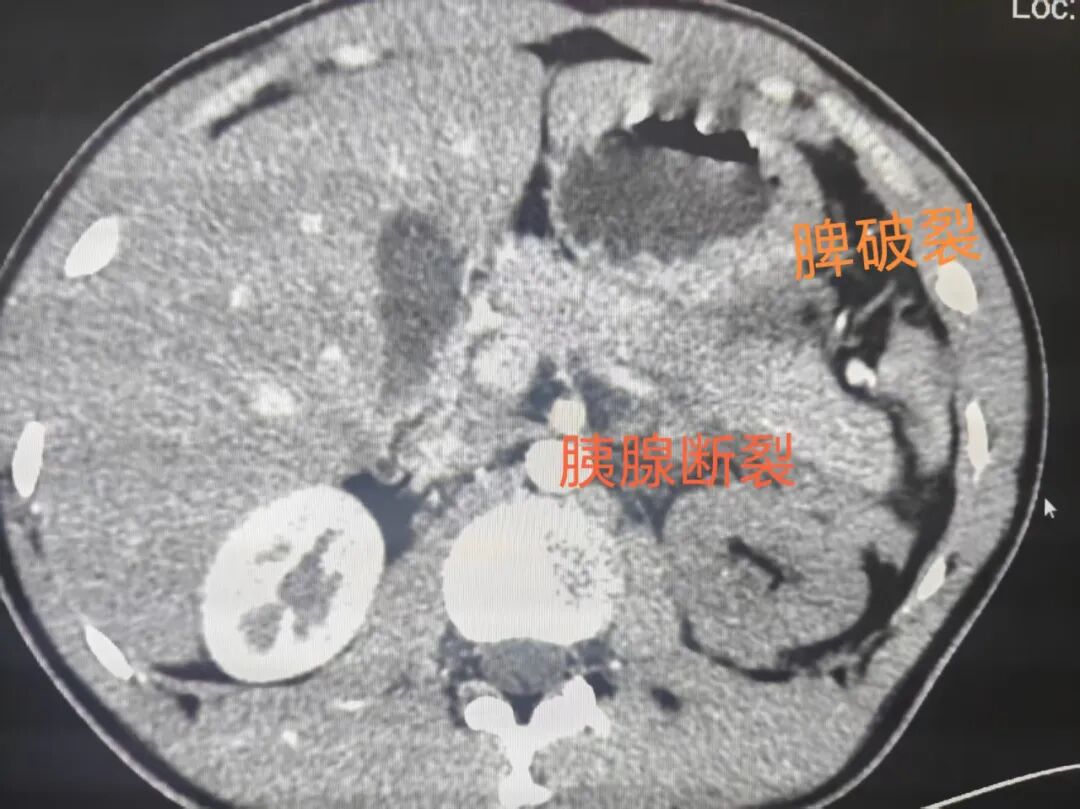

为了排查可能危及生命的隐匿损伤,杨坤当机立断:“立即安排强化CT检查,我亲自陪着去!”在他的全程陪同下,检查快速推进。结果出来的那一刻,所有人都倒吸一口凉气——江措胰腺尾部断裂、脾破裂、左侧肾上腺破裂,多脏器同时受损,已处于危急状态,必须马上进行手术治疗!